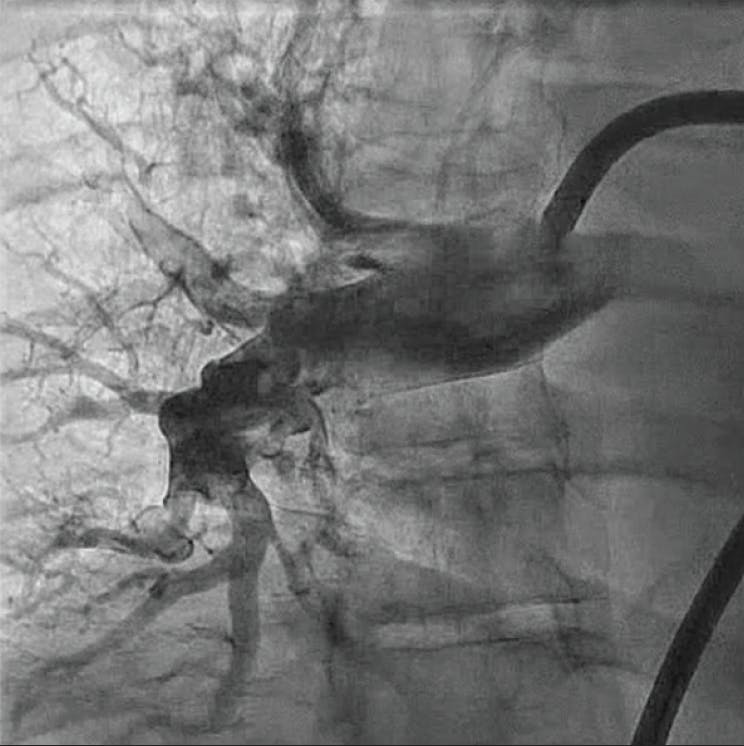

The patient was placed supine on the angiographic table with bilateral groins prepped and draped in sterile fashion. Access was obtained in the right common femoral vein utilizing real-time ultrasound and fluoroscopic guidance with a micropuncture kit with subsequent placement of a 7-F sheath. Over an Amplatz Super Stiff 0.035-inch guidewire (Boston Scientific Corporation), the venotomy was dilated and a 16-F Gore DrySeal sheath (Gore & Associates) was inserted. A 7-F balloon-tipped PA catheter was advanced under fluoroscopic guidance into the right atrium, right ventricle (RV), and left PA, at which time pressures were obtained and cardiac output/index was calculated. Pulmonary angiography of the left PA was performed under digital subtraction angiography, demonstrating large central thrombus occluding the left upper lobe and near occlusive in the left lower lobe.

The Amplatz Super Stiff 0.035-inch wire was advanced through the PA catheter into the left lower lobe. The PA catheter was removed and exchanged for the Lightning Flash 2.0 aspiration catheter with HTORQ tip shape. The wire was removed, and two separate aspirations were performed in the left PA.

Postprocedure angiography demonstrated resolution of thrombus within the left upper and left lower lobes. The estimated blood loss was minimal at 70 mL. Hemostasis achieved with a purse string suture secured with a three-way stopcock. The access-to-closure procedural time was 31 minutes with a total thrombectomy suction time of 1 minute. The patient was transitioned from high-flow nasal cannula on the procedural table and weaned to room air over the next 2 days. He was discharged from the hospital on postoperative day 3 on appropriate oral anticoagulation.

Figure 1. Preprocedural angiogram of the left PA.

Figure 2. Postprocedural angiogram of the left PA.